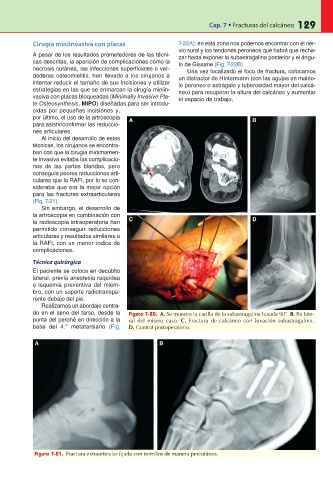

Realizamos un abordaje centra-

do en el seno del tarso, desde la Figura 7-20. A. Se muestra la carilla de la subastragalina luxada 90°. B. Rx late-

punta del peroné en dirección a la ral del mismo caso. C. Fractura de calcáneo con luxación subastragalina.

base del 4.° metatarsiano (Fig. D. Control postoperatorio.